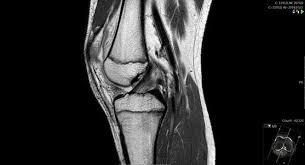

Subesepcialidade- Ortopedista especialista em Joelho

A subespecialidade de joelho trata lesões ligamentares (como o LCA), lesões meniscais, condromalácia patelar, tendinites, artrose e outros problemas que causam dor ou dificuldade de movimento. Também é responsável por procedimentos como infiltrações, artroscopias e cirurgias de reconstrução.

Lesões no joelho são muito comuns em esportes, no envelhecimento e até em pessoas com sobrepeso. O tratamento pode ser conservador ou cirúrgico, sempre buscando devolver estabilidade, força e mobilidade ao paciente.

Quando necessário, são solicitados exames de imagem, como radiografias, ultrassonografias, ressonância magnética ou tomografia computadorizada, para confirmar o diagnóstico e planejar o tratamento mais adequado.

2.Artroscopia

Cirurgia minimamente invasiva feita com pequenas incisões e o uso de uma câmera. É usada para diagnóstico e tratamento de problemas articulares como:

• Lesões de menisco e ligamentos no joelho

• Lesões do ombro (como luxações e ruptura do manguito rotador)

• Sinovites, corpos livres articulares e cartilagem lesionada

• Lesões Condrais, Lesão ligamentares, Lesões tendineas no tornozelo

A recuperação costuma ser mais rápida e com menos dor.